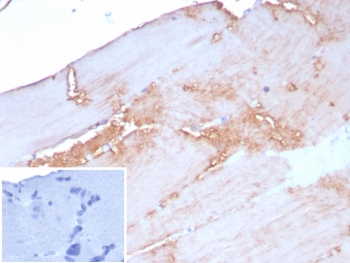

IHC staining of FFPE human skeletal muscle tissue with ACTN2 antibody (clone rACTN2/8177). Inset: PBS used in place of primary Ab (secondary Ab negative control). HIER: boil tissue sections in pH 9 10mM Tris with 1mM EDTA for 20 min and allow to cool before testing.

Immunohistochemistry (FFPE) : 1-2ug/ml for 30 min at RT